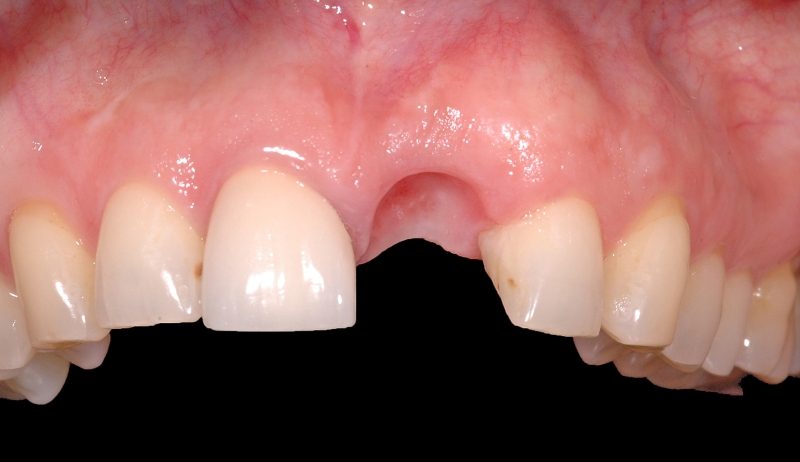

15/18 - Situation after long-term healing with provisional prosthesisGBR together with soft tissue augmentation with mucoderm® and maxresorb® - Dr. S. Scherg